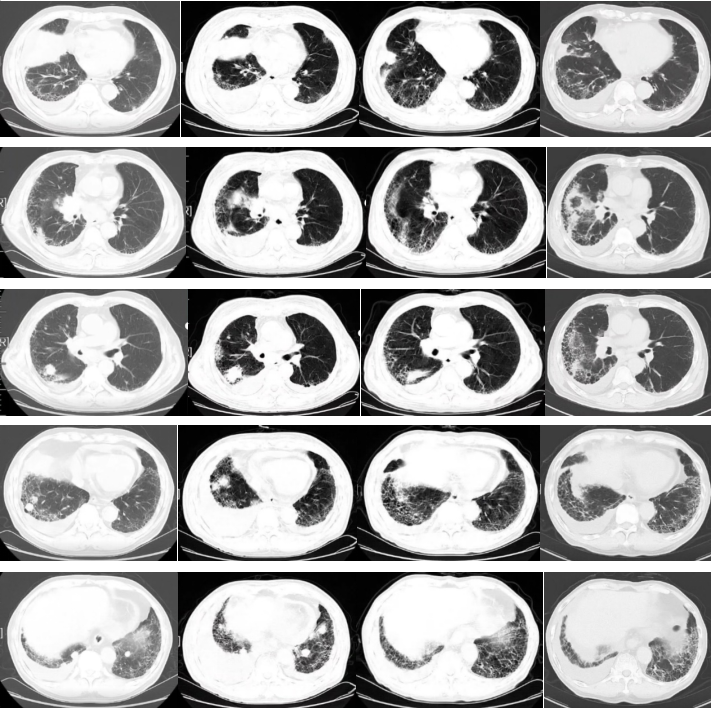

2022-03-31胸部平扫+增强CT:右肺中叶占位(2.6×4.7cm),考虑肺癌,双肺多发小结节(右肺中叶较大者长径约1.8cm),考虑转移。右侧锁区、纵隔及右肺门淋巴结增大(较大者短径约3.2cm),考虑转移。双肺间质性炎。左肺下叶钙化灶。右侧胸腔积液,心包积液。冠状动脉硬化斑块形成。

图1